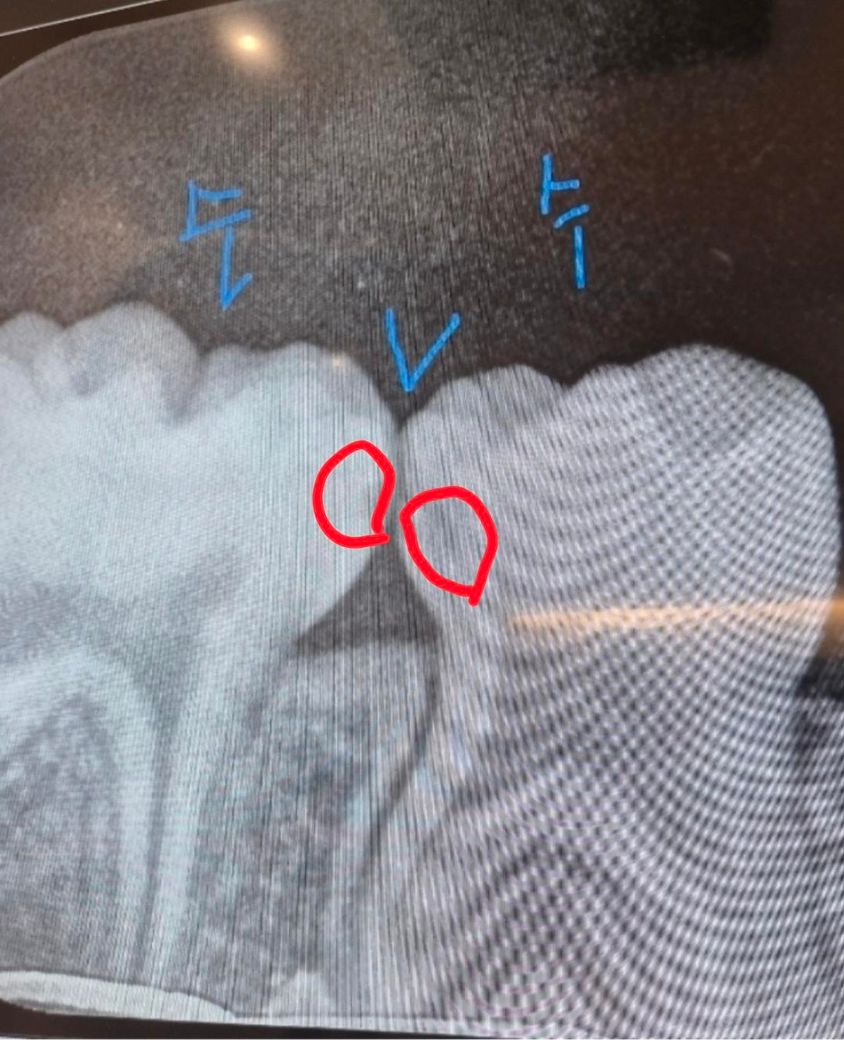

헌재 40개월 만3세 아이입니다 치과에 갔다왔더니 충치가 있다고 레진으로 때워야한다고 하더라과요 3개월정도 지켜보면 어떻냐고 하니까 이건 꼭 충치치료해야한다 안하면 신경치료까지 간다고 하는데, 꼭 해야하는게 맞을까요? 만약 해야한다고 한다면 사진상 빨간색원 왼쪽오른쪽 2개를 다 해야하는건지, 아니면 오른쪽만 하고 왼쪽은 지켜보는게 나을지 어떻게 하는게 좋을까요?

• 1번 째 사진

4. 만3세의 D,E 유치는 제1,2 소구치(영구치)로 대체되기 까지는 아직 시간이 매우 많이 남았습니다. 그래서 충치가 있는 상태에서 불안하게 유지를 하기 보다는 2개 다 치료를 해주는 것이 바람직합니다.

5. 또한 방사선 사진상 보이는 옆면 충치는 비교적 빠르게 충치가 진행되기도 하고, 그쪽으로 계속 음식물이 껴서 관리가 더 어렵기도 합니다.

6. 방사선 사진상에서 보이는 충치보다 실제로 충치는 더 크게 진행되었을 수도 있습니다.

아이들은 충치가 상당히 빨리 진행됩니다. 치아 둘다 사이에 충치가 잇는거 같습니다. 더 진행되기 전에 레진으로 치료를 하시는게 좋을것같습니다.

방사선사진에서는 인접면에 충치가 있는것으로 보입니다. 아이들의 경우 충치가 쉽게 커질수 있기 때문에 예방적으로 치료를 하는경우가 많습니다.